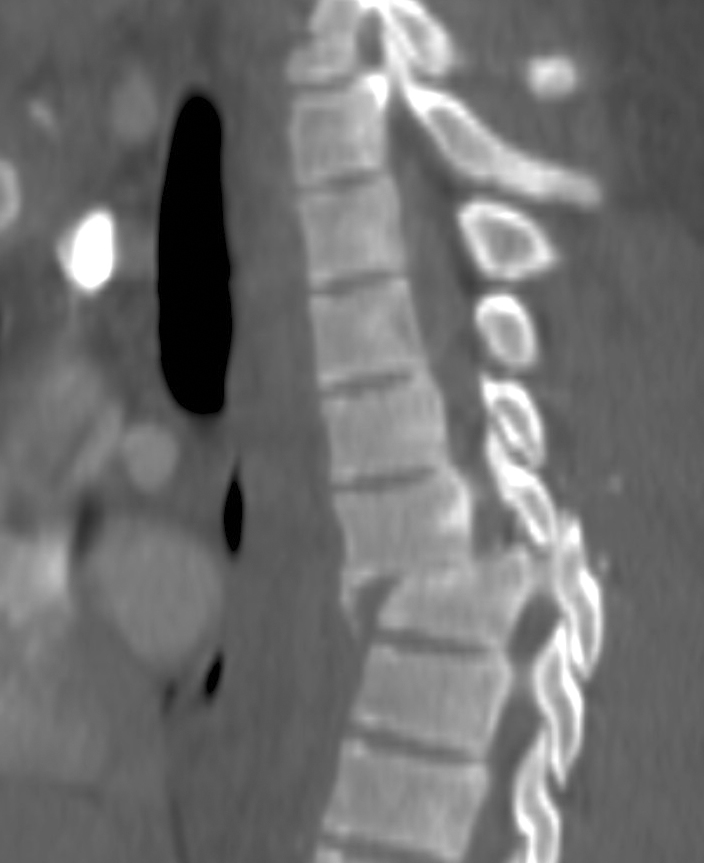

Gallery Blunt Chest Trauma Spine trauma Case 7d

Case 7d